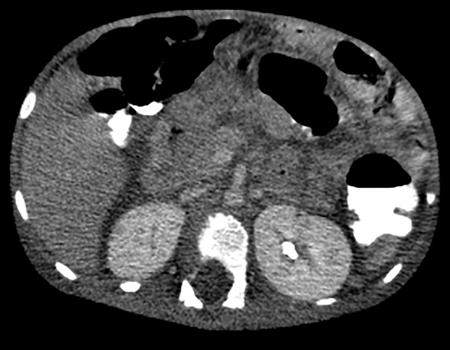

Anmol Bhatia, Ajay Prashanth Dsouza, Kushaljit Singh Sodhi Urinary tract infection (UTI) is a common cause of febrile illness in children, second only to respiratory tract infections. The incidence before 14 years of age ranges from 3%–10% in girls and 1%–3% in boys; however, the incidence is more in boys during infancy. The clinical spectrum in increasing order of severity ranges from asymptomatic bacteriuria and cystitis to acute pyelonephritis and septicemia. Urinary tract anomalies, prematurity, indwelling urinary catheters, lack of circumcision in boys and high-grade vesicoureteral reflux (VUR) are some of the common predisposing factors. Although the clinical outcome is good in most patients, a few may develop long-term complications like hypertension, chronic renal insufficiency and end-stage renal disease. Given the poor localizing signs and the dreaded complications, a high degree of clinical suspicion, prompt diagnosis and treatment and tailored follow-up play pivotal role in management of these patients. Urine culture is the most important tool to establish the diagnosis and identify the causal pathogen, Escherichia coli being the most commonly isolated bacteria. Midstream clean catch urine sample is used in toilet-trained children while the sample is often obtained by suprapubic aspiration or transurethral catheterization in younger age group. A colony count of >105 CFU/mL of a single species in a midstream clean catch sample is confirmatory. Although imaging can aid in the diagnosis of an ongoing UTI, the main role lies in identifying the associated urinary tract abnormalities and also to look for the extent of consequent renal insult. Some of the common anatomic abnormalities predisposing to recurrent and complicated infections include VUR, congenital pelviureteric junction (PUJ) obstruction, ureterocoele, posterior urethral valve, ureteral duplication and neurogenic bladder. The imaging modalities commonly used in children are ultrasound (US), which helps in detection of structural anomalies, hydroureteronephrosis, urinary tract stones and renal scars; voiding cystouretherography (VCUG) for detecting VUR and 99mTc-labelled dimercaptosuccinic acid (DMSA) scans to look for renal scars. US is often used as the first-line imaging modality because of its easy availability, low cost, non-invasiveness and lack of ionizing radiation. UTI, when confined to the lower genitourinary tract, frequently called as cystitis, reveals diffuse bladder wall thickening (Fig. 10.8.1A) with hazy margins on grey-scale US, which may show increased vascularity on Doppler (Fig. 10.8.1B). Floating echoes in the urine are commonly seen. The distal ureter may also be dilated and show mural thickening. Since UTI confined to bladder is mostly uncomplicated, it does not usually warrant a further imaging workup. However, in cases of severe bladder trabeculations, unilateral gaping ureteral ostium, open bladder neck, follow-up for bladder outlet obstruction, dysfunction or VUR may be indicated after the acute infection settles. Inflammatory response to the infection leads to swelling and decreased perfusion in renal parenchyma. Findings on intravenous urography (IVU) include renal enlargement, a diffuse or patchy striated nephrogram with delayed opacification and effacement of pelvicalyceal system. On renal US, diffuse or localized renal enlargement may be the only finding. Other typical findings include altered parenchymal echotexture, usually hypoechoic (Fig. 10.8.2) but may be hyperechoic, along with poor corticomedullary differentiation. Colour or power Doppler study reveals reduced vascularity. On 99mTc DMSA or glucoheptonate scans, photopenic defects due to reduced accumulation of renal cortical tracers are seen. The defects may be solitary, multiple or may involve the entire kidney giving a mottled appearance. DMSA renal scintigraphy with a sensitivity of 99.9% is the imaging modailty of choice for diagnosing acute pyelonephritis (APN). Among the patients with UTI, 50%–91% show defects on nuclear scans, suggestive of acute pyelonephritis. When both VUR and APN are present, scintigraphy is abnormal in 79%–86% of children. Permanent scars are known to occur in 38%–57% of children diagnosed with APN on nuclear scan, not withstanding the grade of VUR. 99mTc DMSA scan is the imaging modality of choice for detection of renal scars and they also appear as photopenic defects; however, the temporal course of study helps to differentiate it from APN. Thus, follow-up scanning at 3–6 months may be suggested to detect if the kidney has healed or scarred. CECT reveals striated nephrogram along with multiple wedge-shaped or round hypoenhancing areas with apices directed towards calyces (Fig. 10.8.3). Perinephric fat stranding may also be seen. MRI reveals wedge-shaped or round, T2 hyperintense lesions with decreased signal on inversion recovery sequences. And similar to CECT, striated nephrogram and inflammatory changes in perinephric fat may be demonstrated. MRI can also help in detection of renal scars. Despite it being a radiation-free modality with utility in poor renal function, MRI is less often used due to limited availability, higher cost, longer scan times and need for prolonged sedation. Acute focal bacterial nephritis is a localized or segmental form of acute pyelonephritis, also known as acute lobar nephronia, usually affecting only a renal pole or one moiety in a duplex kidney. It appears as an ill-defined, poorly marginated mass in contrast to renal abscess which is relatively well-defined, surrounded by enhancing walls (Fig. 10.8.4). The mass is usually hypoechoic on USG with low-level internal echoes and shows reduced vascularity on Doppler. CECT shows ill-defined or wedge-shaped hypodense areas which correspond to focal photopenic defects on nuclear scans.